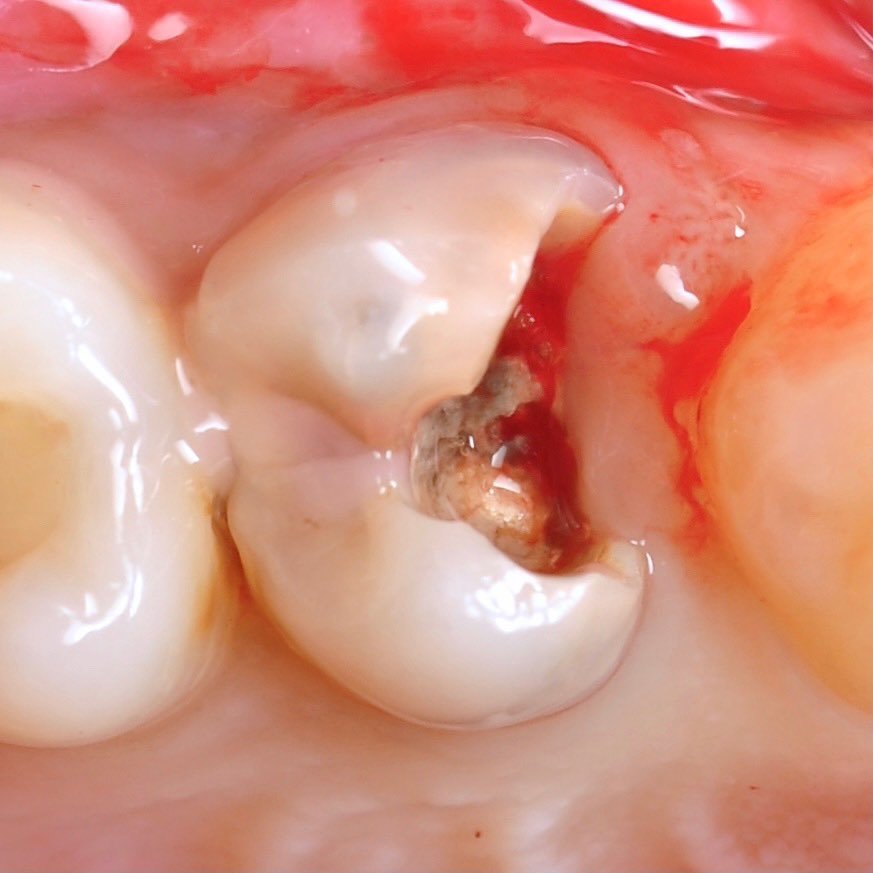

Successful endodontic treatment requires careful preparation, disinfection and sealing of the canals.

• Easily locate the entrance to the canal with maximum preservation of the tooth structure.

• Identify additional canals and anatomical features.

• Control the removal of pulp and organic tissue from the canal, which protects us from secondary infection.

The most common complication encountered by the dentist during endodontic treatment is perforation and instrument breakage in the canal, resulting in the majority of patients losing a tooth. We can easily deal with such difficulties through a microscope.